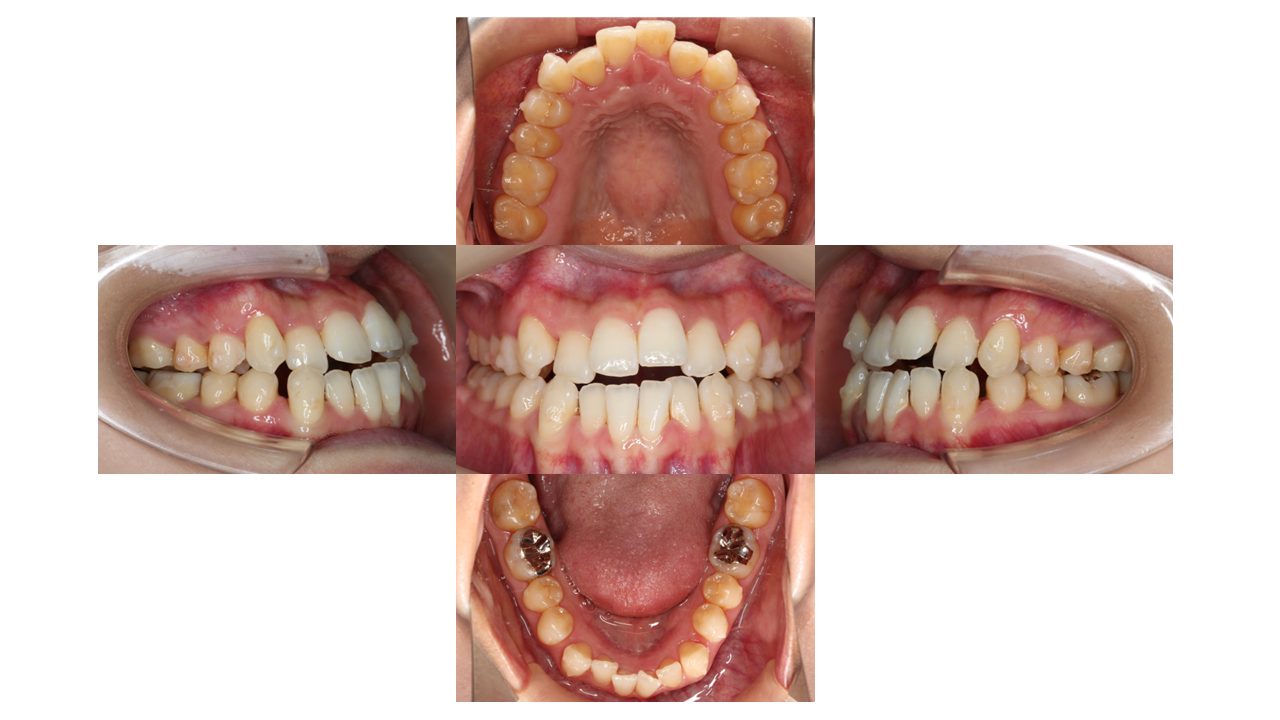

1年5カ月経過の口腔内の状態です。